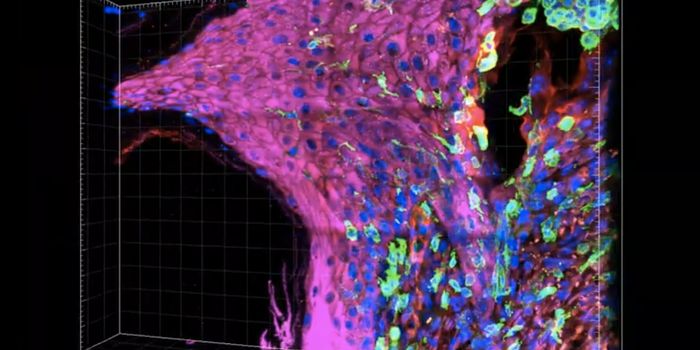

SEP 24, 2021Cell & Molecular BiologyThis photo by Sozen & Jorgensen et al., Nature Communications, shows an embryo-like structure made from human stem cells ...